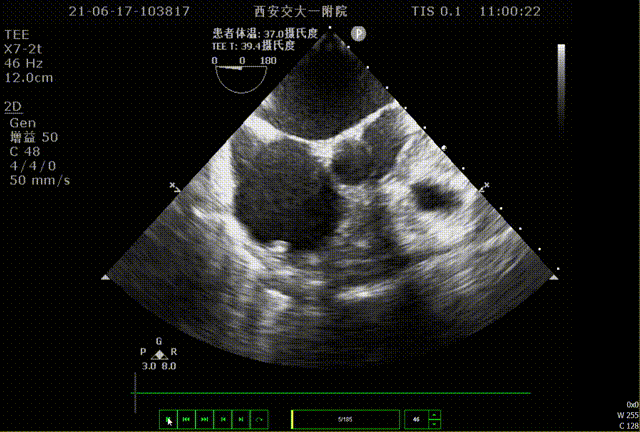

术前TEE评估

术前排除左心耳血栓,左心耳可能呈反鸡翅型,心耳偏小,梳状肌发达。

0°TEE

该患者左心耳开口较小,呈反鸡翅型,开口处即反折,同时内部梳状肌发达,且深度较浅,因此手术难度偏大,术前安排进一步CT评估以协助制定手术策略。